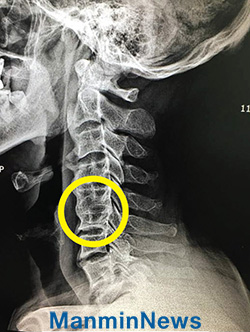

9 апреля я захотел получить молитву старшего пастора д-ра Джей Рока Ли, но мне это не удалось. Поэтому я написал желание своего сердца на ладони: «Позволь мне переехать в хороший дом и исцели меня от грыжи шейного отдела позвоночника». После того как я пожал ему руку с верой, боль исчезла. На следующий день я почувствовал себя лучше и уже смог медленно повернуть голову.

Чтобы получить полноценный ответ, я, взяв пост, стал искренне готовиться к мужскому и женскому служению посвящения. Я слушал проповеди старшего пастора, молился и старался измениться. А тем временем, мне удалось найти хороший дом по разумной цене, где я могу жить. 14 мая, во время служения посвящения, я был полностью исцелен от грыжи шейного отдела позвоночника. И я легко, без проблем, поворачиваю голову.

5-й и 6-й шейные позвонки Он мог смотреть только вперед, но был исцелен.  Теперь он без проблем поворачивает головой.